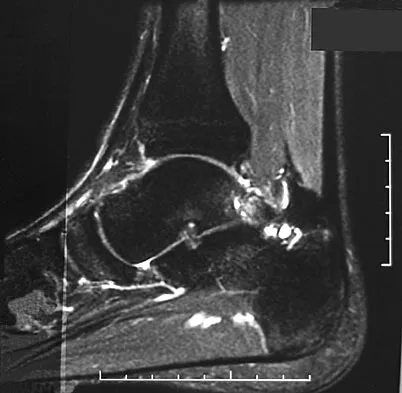

A 28-year-old professional dancer reports a 3-month history of progressive pain in the posterior aspect of the left ankle. Her symptoms are worse when she assumes the en pointe position. Examination reveals tenderness to palpation at the posterolateral aspect of the ankle posterior to the peroneal tendons which is made worse with passive plantar flexion. There is no nodularity, fluctuance, or tenderness of the Achilles tendon. The neurovascular examination is unremarkable. A lateral radiograph and MRI scan are shown in Figures 16a and 16b, respectively. Management should consist of

The imaging studies reveal findings typical of the os trigonum syndrome. This condition results from inflammation between the os trigonum and the adjacent talus. The symptoms of posterior ankle pain are exacerbated by plantar flexion, which stresses the fibrous union between these two bones. Definitive management of the high-level athlete involves excision of the os trigonum from a medial approach, although arthroscopic excision has also been described. The os trigonum is not an intra-articular structure; therefore, ankle arthroscopy is neither diagnostic nor therapeutic. Abramowitz Y, Wollstein R, Barzilay Y, et al: Outcome of resection of a symptomatic os trigonum. J Bone Joint Surg Am 2003;85:1051-1057. Mouhsine E, Crevoisier X, Leyvraz P, et al: Post-traumatic overload or acute syndrome of the os trigonum: A possible cause of posterior ankle impingement. Knee Surg Sports Traumatol Arthrosc 2004;12:250-253.